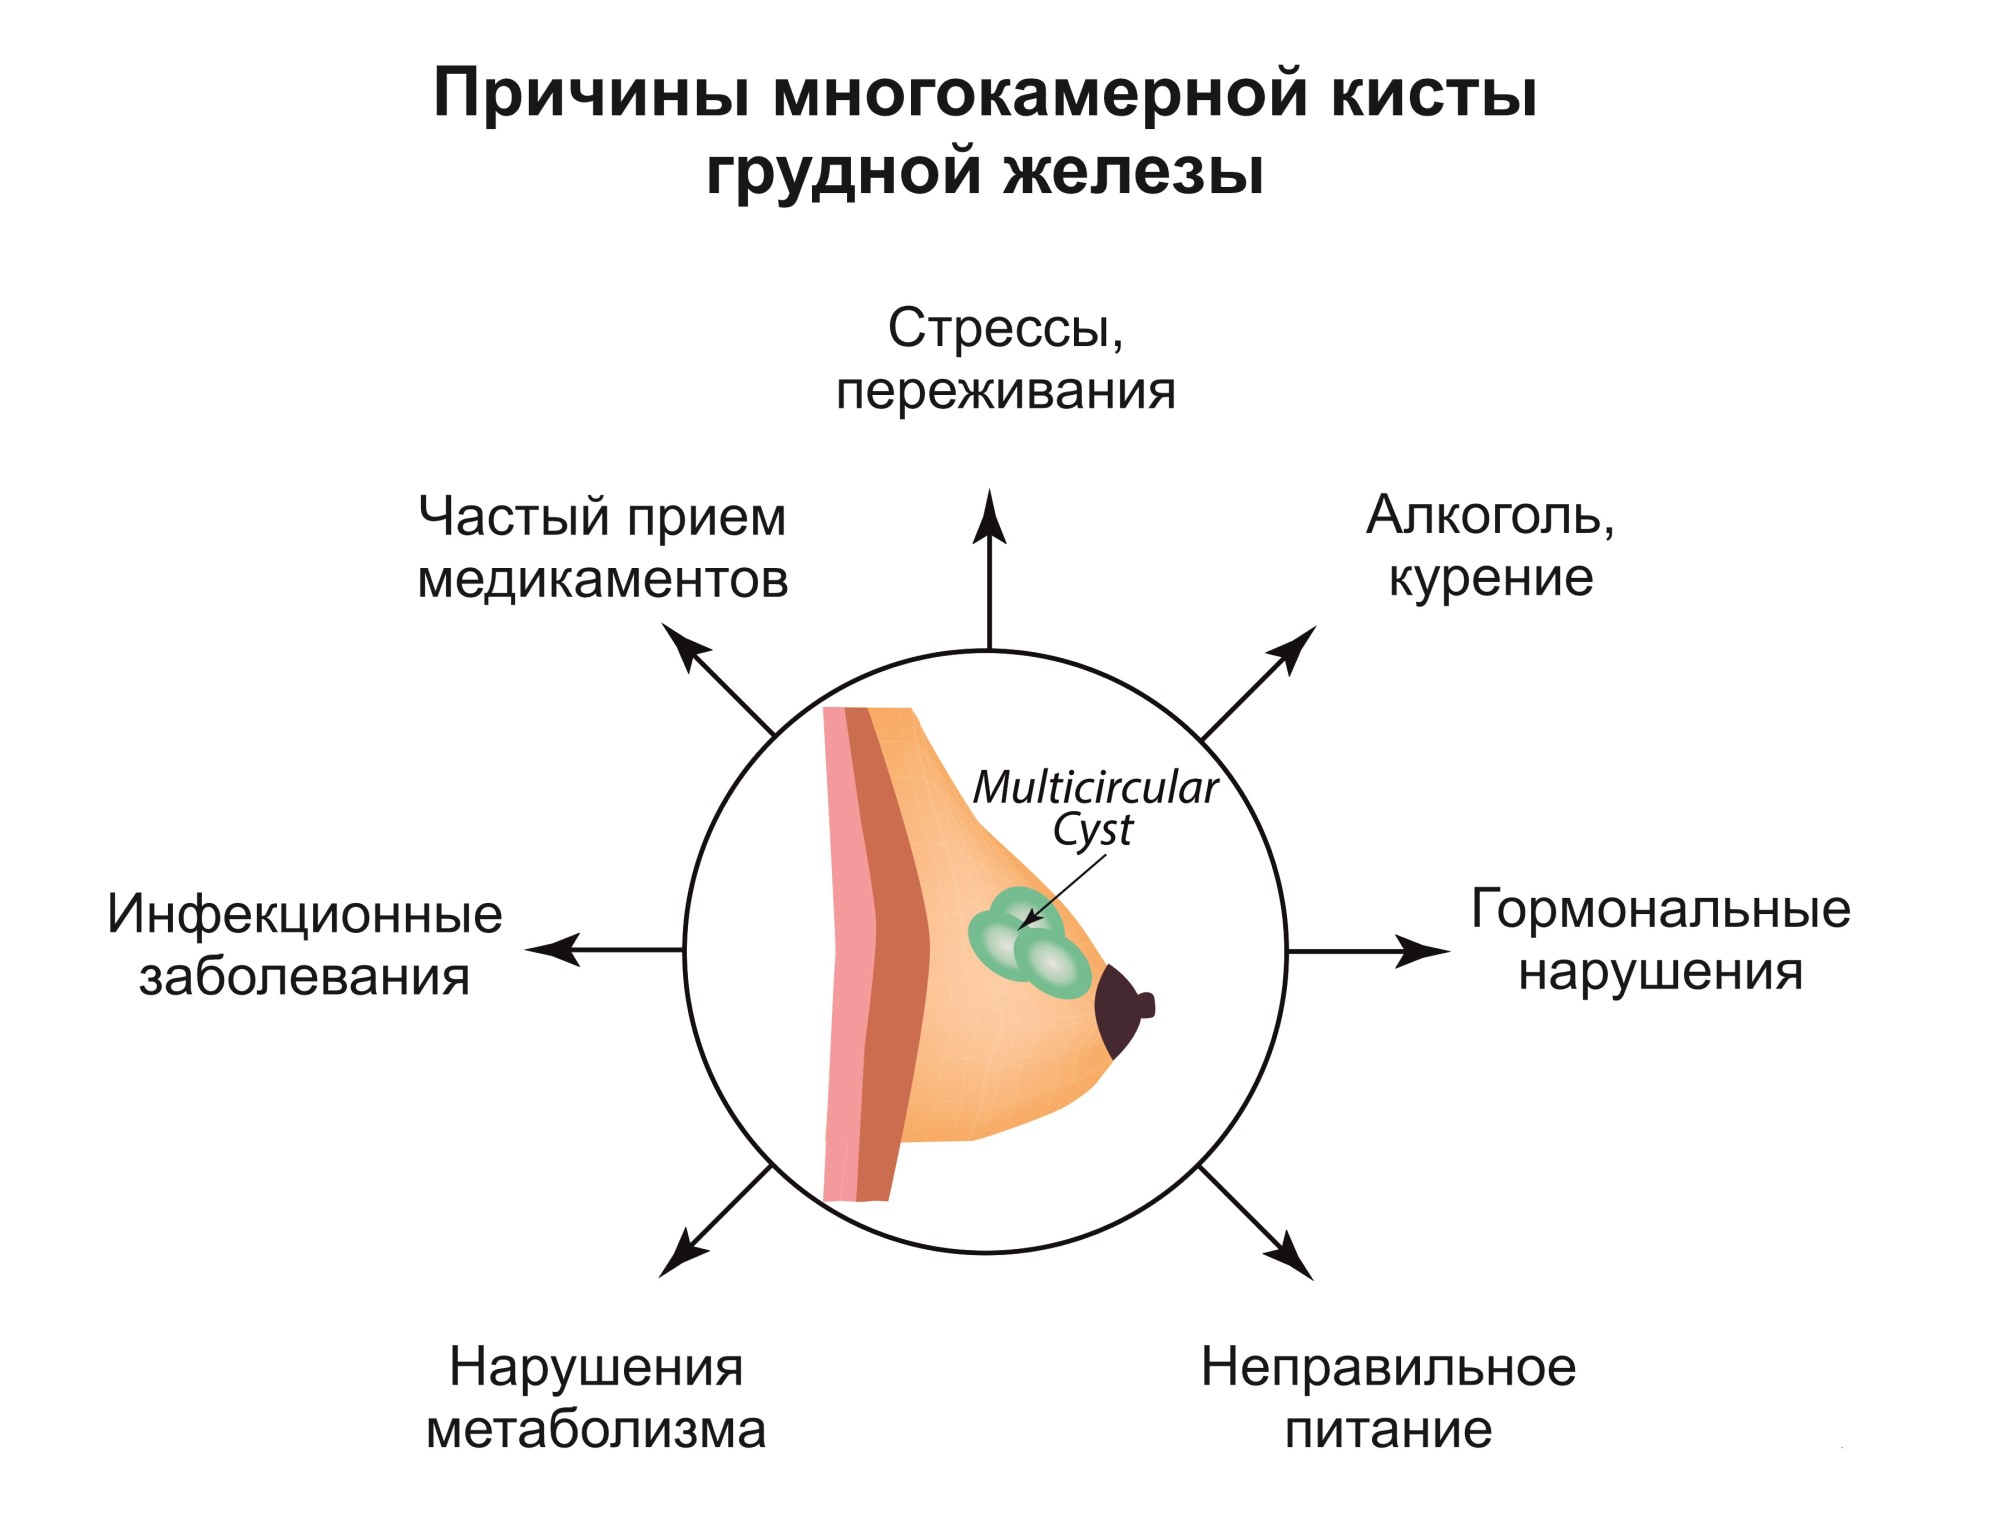

Фиброаденома молочной железы - доброкачественное образование, которое часто встречается у женщин. Оно может быть обнаружено при помощи различных методов диагностики, включая маммографию. Ниже представлены фотографии, помогающие понять, как выглядит данное заболевание.